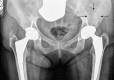

Dual mobility cups in total hip arthroplasty

Total hip arthroplasty (THA) is considered one of the most successful surgical procedures in orthopaedics. With the increase in the number of THAs performed in the world in the next decades, reducing or preventing medical and mechanical complications such as post-operative THA instability will be of paramount importance, particularly in an emerging health care environment based on quality control and patient outcome. Dual mobility acetabular component (also known as unconstrained tripolar implant) was introduced in France at the end of the 1970s as an alternative to standard sockets, to reduce the risk of THA dislocation in patients undergoing primary THA in France. Dual mobility cups have recently gained wider attention in the United States as an alternative option in the prevention and treatment of instability in both primary and revision THA and offer the benefit of increased stability without compromising clinical outcomes and implant longevity. In this article, we review the use of dual mobility cup in total hip arthroplasty in terms of its history, biomechanics, outcomes and complications based on more than 20 years of medical literature.